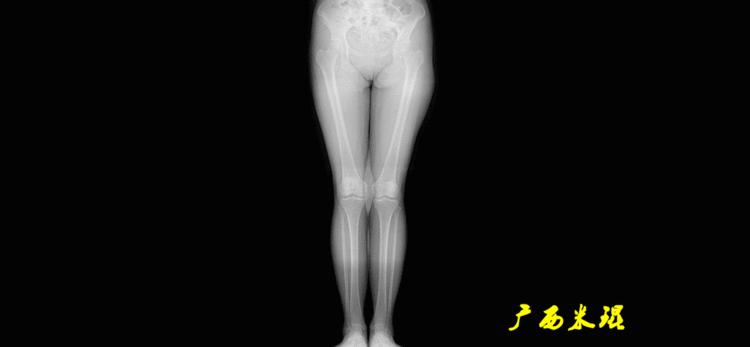

最常见的下肢畸形发生于冠状面,即膝内外翻畸形,冠状面的对线异常通过应用“对线异常检验”进行分析,机械轴的偏移(MAD)表现为对线异常。

膝内翻是指下肢力线通过膝关节中心点内侧,距中点2mm以上,偏内超过15mm为显著膝内翻。膝外翻是指下肢力线通过膝关节中心点外侧,距中点2mm以上,偏外超过10mm为显著膝外翻。

无论如何,拍摄出来的下肢全长片必须包含髋关节中心、膝关节中心及踝关节中心,否则对临床是无用的。有了一张下肢的全长照片,我们需要确定下肢关节的中心点,通过中心点画出下肢的各种轴线,然后利用轴线与关节线的相交得出各种所需要的角度。